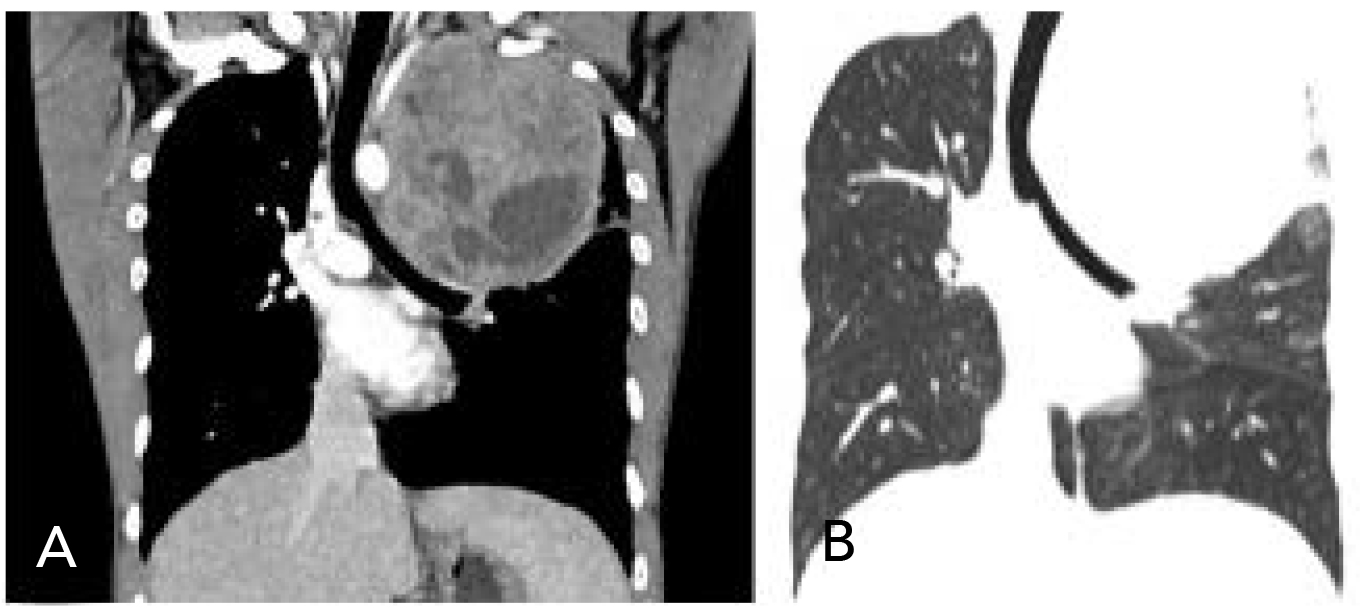

Después de ello se le tomó al paciente una tomografía contrastada que, en el plano axial, en el hemitórax izquierdo, mostró una tumoración que involucraba los segmentos apicoposterior y anterior del lóbulo superior y el segmento apical del lóbulo inferior. Medía aproximadamente 10.9 cm x 12.3 cm x 14.4 cm en sentido latero-lateral, anteroposterior y cefalocaudal, con densidad heterogénea (figura 2). Se observaron áreas sólidas que realzaban tras la administración de medio de contraste intravenoso, con zonas de necrosis de predominio en la mitad inferior. Los bordes eran lobulados e infiltraba la grasa mediastinal. En el corte coronal, se visualizó un efecto masa que desplazaba la tráquea, la carina y los bronquios, en sentido contralateral (figuras 3A y 3B).

Figura 2. Tomografía contrastada, corte axial de hemitórax

Figura 3. Tomografía contrastada, en reconstrucción coronal. A) Masa heterogénea en el pulmón izquierdo que desplaza la tráquea en sentido contralateral. B) Ventana pulmonar